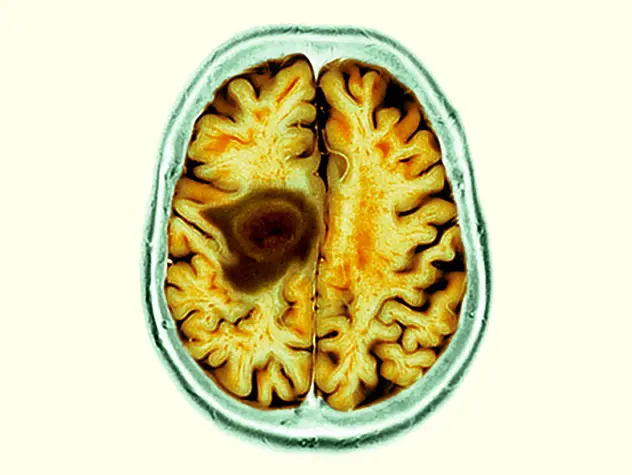

Innovative technologies and alternatives to traditional treatments are transforming the diagnosis and management of neurological conditions. In 2025, NewYork-Presbyterian physicians and surgeons from Columbia and Weill Cornell Medicine used sonication and convection-enhanced delivery to penetrate the blood-brain barrier, validated an adjunctive treatment for subdural hematoma, broadened access to spine surgery, advanced experimental therapies for neurodegenerative diseases, and more. Our specialists have been steadfast in reshaping the fields of neurology and neurosurgery in the pursuit of better patient outcomes and enhanced quality of care.

From cutting-edge research to compassionate patient practice, neurologists and neurosurgeons from Columbia and Weill Cornell Medicine are at the forefront of developing and applying the most advanced approaches to treat debilitating conditions affecting the brain and spine. With a broad range of focus on neurodegenerative and neurovascular disorders to malignant tumors, our innovative and advanced care is leading to new treatment options and enabling patients to achieve the best possible outcomes.